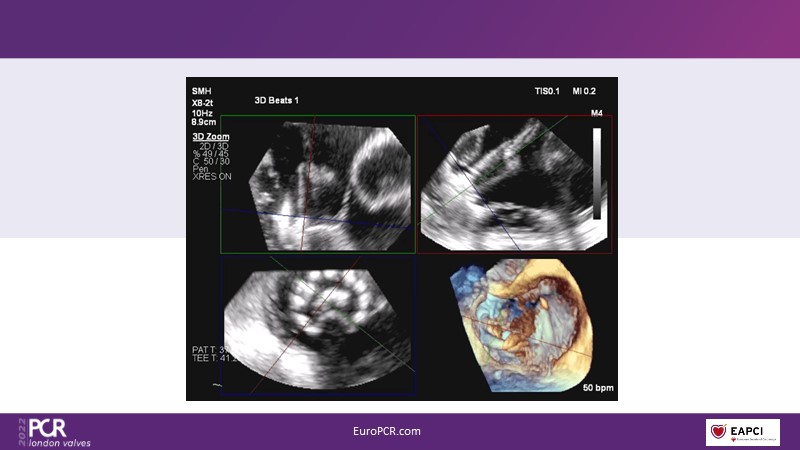

The right valves for the right ventricle: Venus MedTech tricuspid and pulmonary replacement systems

In this session from PCR London Valves 2022, discover the new Venus MedTech technology for tricuspid and pulmonary valve replacement, and a review of the clinical indications, selection criteria and procedural details.

- To learn more about the clinical experience and outcomes with Cardiovalve tricuspid and Venus P-valve